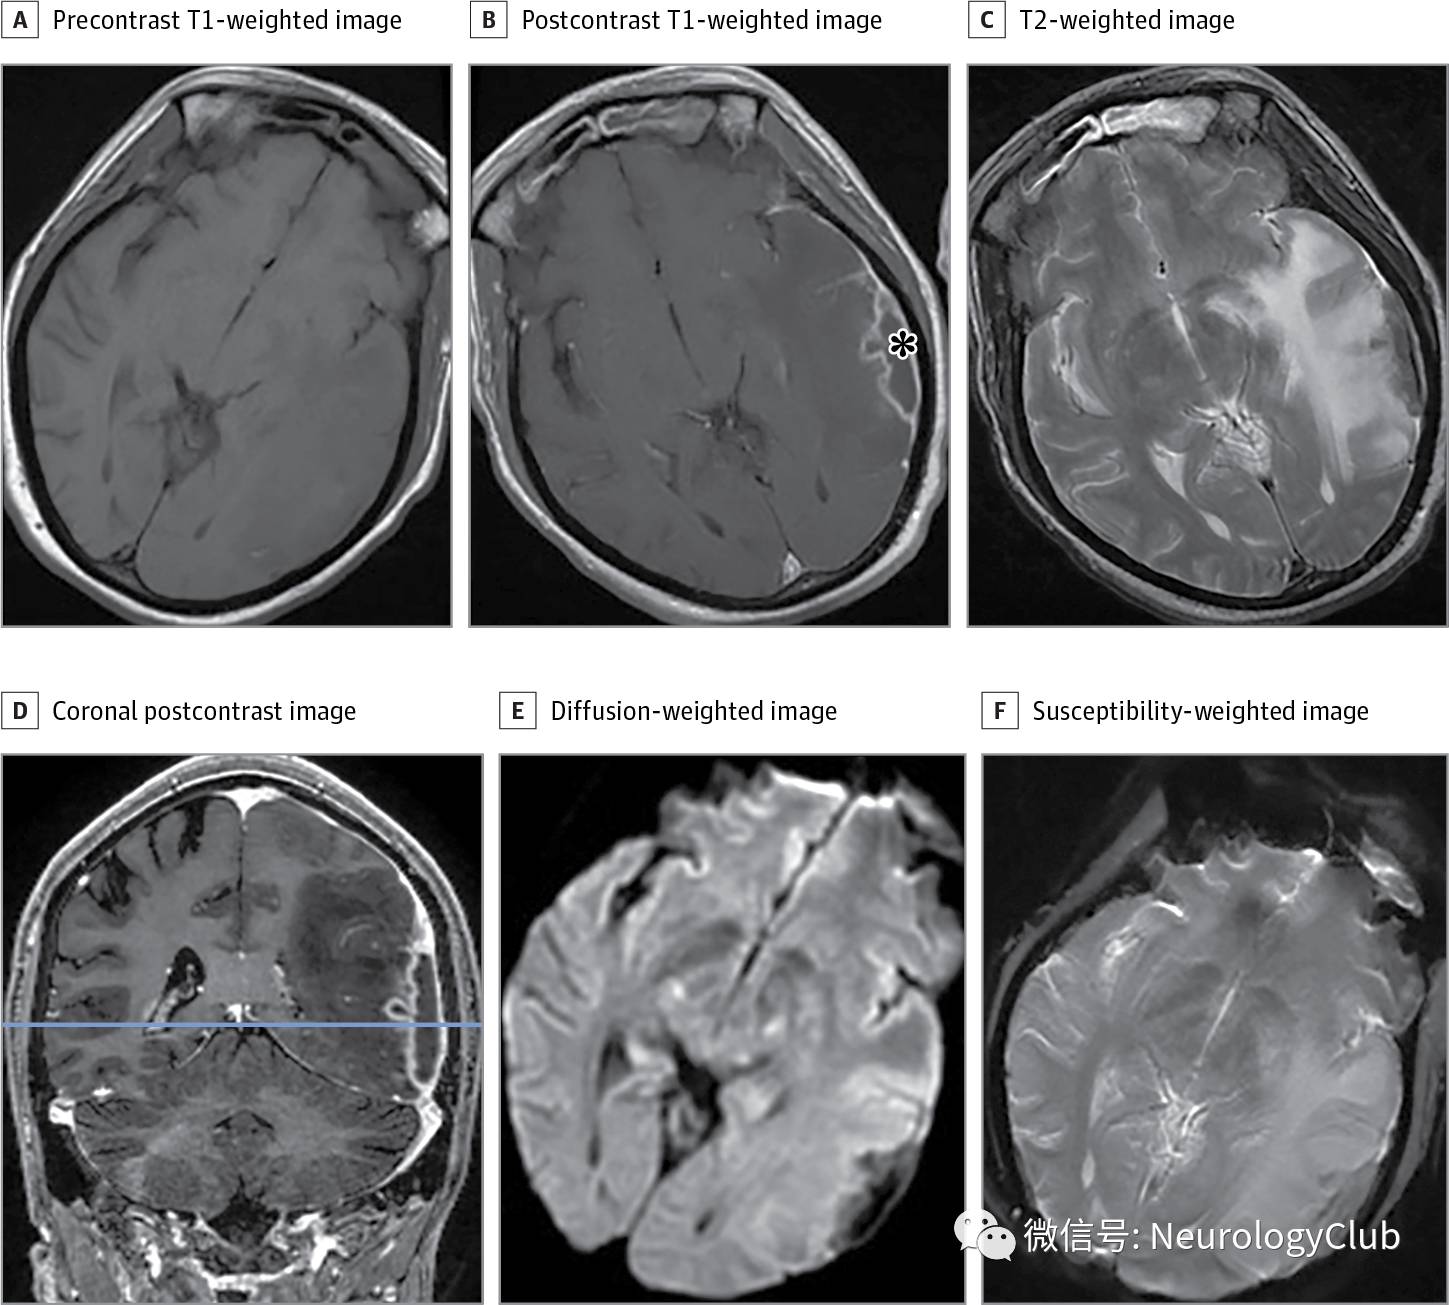

(图:A:T1WI;B:T1增强可见不规则环形强化[*为活检部位];C:T2WI可见广泛水肿;D:冠状位T1增强可见弥漫硬脑膜强化;E:DWI未见结核瘤内弥散受限;F:SWI未见出血)

头颅MRI提示左侧顶叶病灶伴周围水肿,增强后可见不规则环形强化(图)。病灶呈不规则且处于萌芽期外观,无弥散受限,提示结核瘤可能。根据中枢神经系统结核病经验性治疗方案,患者抗生素调整为利福平、异烟肼、吡嗪酰胺、左氧氟沙星和地塞米松。

中枢神经系统结核病常由血行播散所致。多伴有免疫抑制,可表现为软脑膜炎,脑炎和结核瘤。结核瘤指单个或多个分离的占位性病变,常见临床症状包括头痛,发热和癫痫发作。影像学有助于将其与其他化脓性细菌性脓肿区别开来。脑脓肿DWI上普遍有弥散受限,但在结核瘤中少见。结核瘤伴中心干酪样坏死在T2WI上呈等或低信号,无弥散受限。然而,结核瘤伴液化性坏死T2WI上为高信号,可有弥散受限。颅内结核瘤的标准治疗方案包括异烟肼、利福平、吡嗪酰胺和乙胺丁醇。添加地塞米松是出于患者可能出现结核性脑膜炎的考虑。